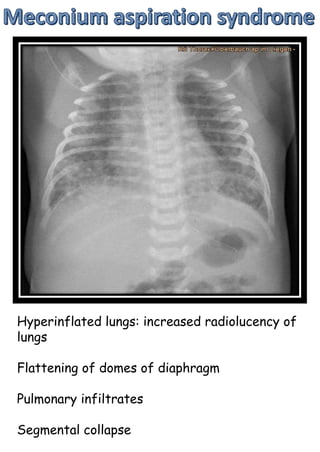

Hyperinflated lungs: increased radiolucency of

lungs

Flattening of domes of diaphragm

Pulmonary infiltrates

Segmental collapse

Hyperinflated lungs: increasedradiolucency of lungs Flattening of domes of diaphragm Pulmonary infiltrates Segmental collapse